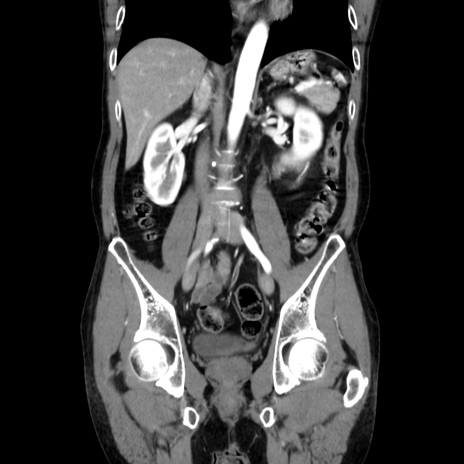

症例37(冠状断像)

【症例】40歳代 男性

【主訴】腹痛

【現病歴】4時間ほど前に電車に乗車中に臍部上より腹痛出現。徐々に増悪し起立困難となり、救急外来受診。生ものは数日食べていない。今朝お雑煮を食べた。

【身体所見】BT 36.8℃、BP 117/84mmHg、HR 91/min、SpO2 97%、苦悶様、腹部:臍上部広範囲圧痛あり、反跳痛±

【データ】WBC 8100、CRP 0.03